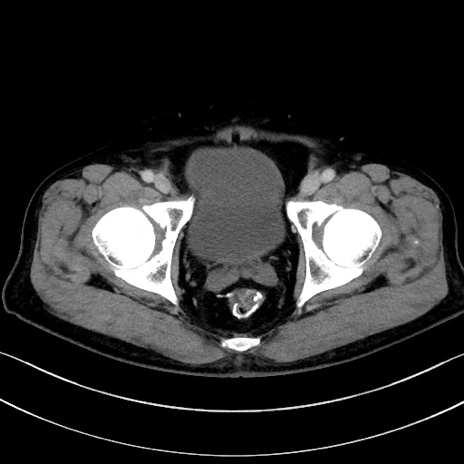

症例15(横断像)

【症例】70歳代男性

【主訴】腹痛

【現病歴】今朝から腹痛あり。全体的に痛い。特に左上の方。排ガスが今日はない。冷や汗が出る。

【既往歴】直腸癌術後

【身体所見】左側腹部〜上腹部に圧痛あり。腹膜刺激症状明らかなではない。軽度反跳痛。左下腹部に術後瘢痕あり。

【データ】WBC 7700、CRP 0.02